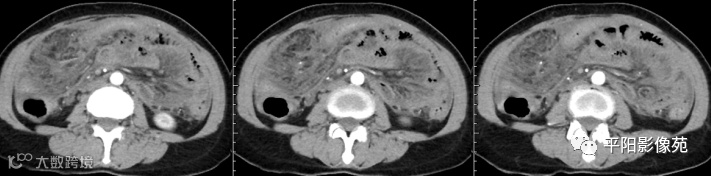

腹部增强 延迟期

壁腹膜增厚伴或不伴腹水;增厚的腹膜光滑、均匀,呈线带状,部分可见腹膜结节,网膜及肠系膜广泛浸润性改变;增强扫描明显强化。

纤维性或干性结核性腹膜炎:不常见,分隔性腹水、巨大网膜团块和肠袢分离或固定

干型:干酪性肠系膜淋巴结病、纤维粘连、增厚,网膜饼状改变

纤维型:网膜饼状团块